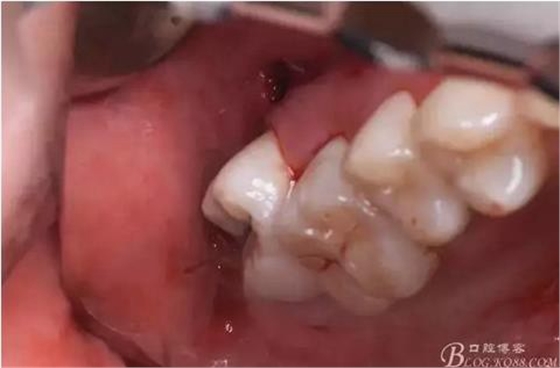

圖6.翻瓣、暴露骨面